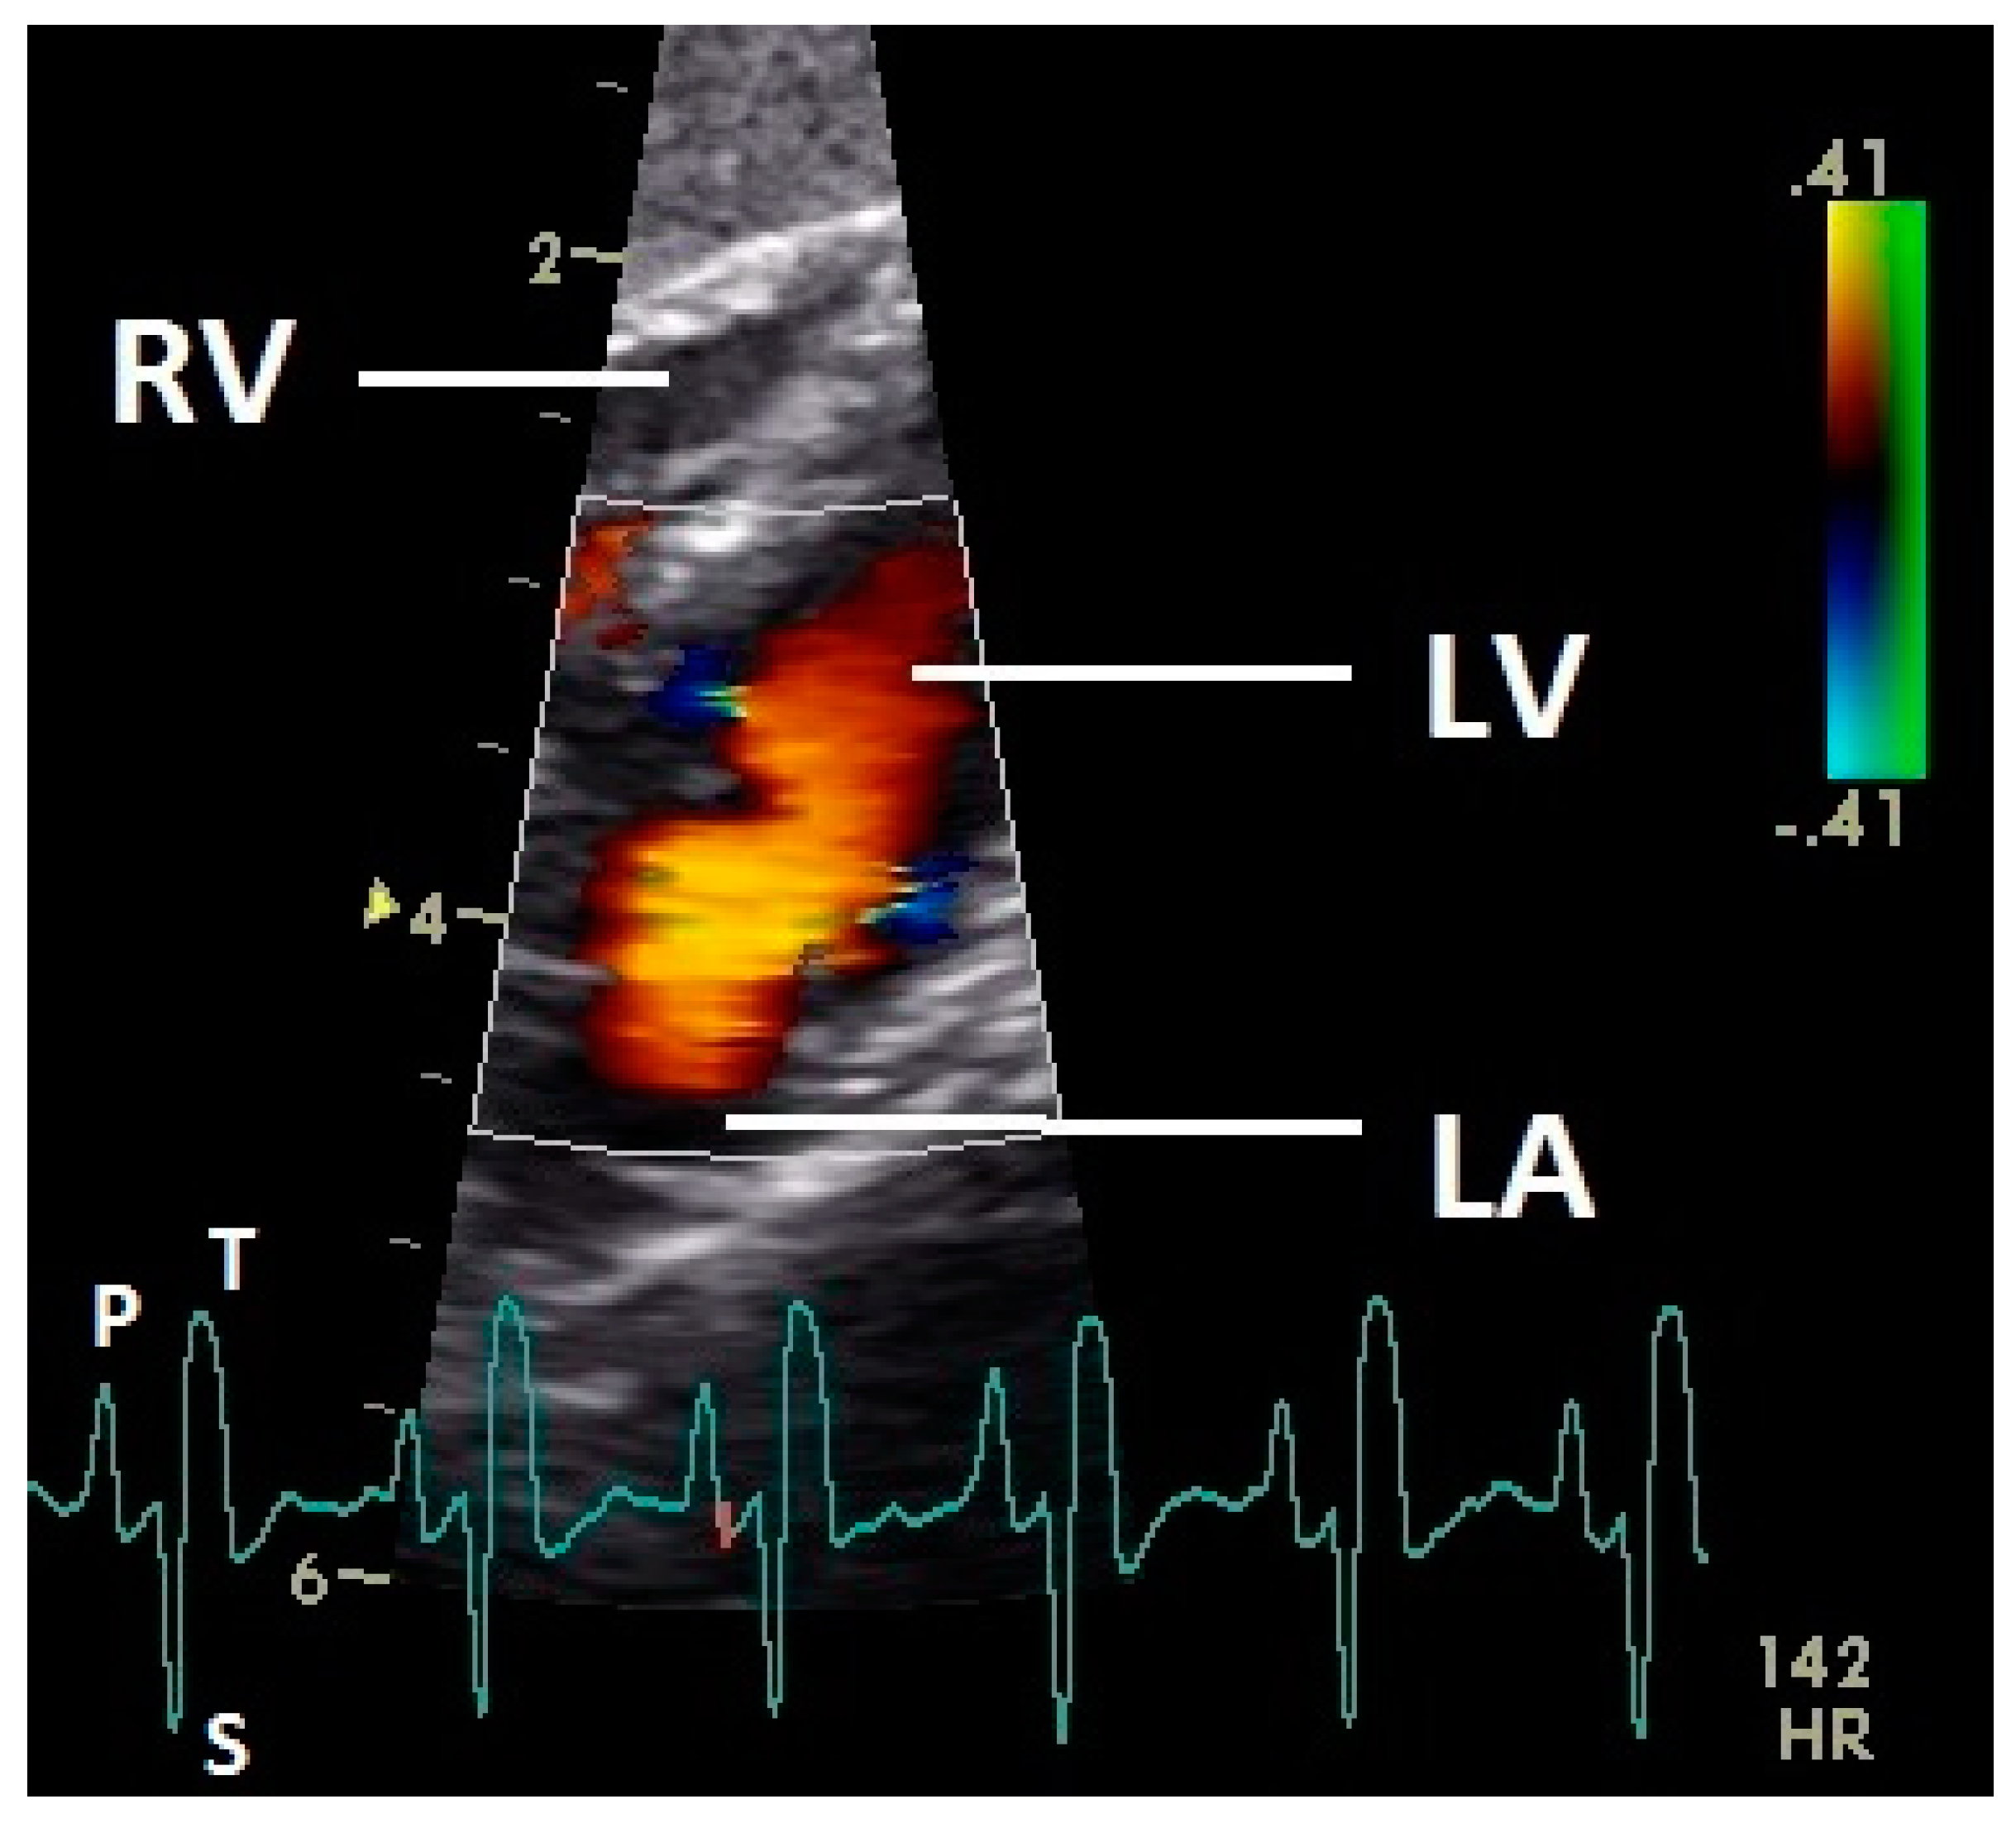

Diastolic ventricular inflow was recorded in the atrium, across the AV valve and within the ventricular inlets and outlets. In the early diastole a red signal was recorded within the left atrium and across the mitral valve annulus into the left ventricle. This phase was interpreted as the passive ventricular filling due to left ventricular relaxation (descending part of T wave in ECG). Behind the longer septal part of the left AV valve leaflet and in the left outflow tract a blue signal in this phase of the cardiac cycle simultaneous to the red signal was observed in 42 birds (97.7%; Figure 1) and in the area of the lateral smaller parts of the left AV valve only in nine birds (20.9%; significant difference Chi-squared test p ≤ 0.001). In the mid diastolic phase in some pigeons the movement of the blood in the ventricle was observed (Figure 2). Within the P wave of the ECG an intense red blood flow signal was evident in the left atrium, crossing the left AV valve and entering the left ventricle as a sign of blood flow caused by atrial contraction. This rapid ventricular filling led to a visible blue signal in the left outflow tract, behind the septal part of the AV valve (97.7%), and in the some pigeons (48.8%; significant difference Chi-squared test p ≤ 0.001) also behind the smaller lateral leaflets of the left AV valve simultaneous to the red signal (Figure 3). In one pigeon the passive diastolic inflow was connected with the active ventricular filling (EA wave).

Figure 2.

Color Doppler image of the ventricle in mid diastolic phase. The vortex formation of the blood in the ventricle is visible (red and blue signal). LV: left ventricle; LA: left atrium; HR: heart rate. Electrocardiogram: P: P wave, S: S wave, T: T wave. The color scale on the right of the image is calibrated in m s−1.

Figure 3.

Color Doppler image of the late active filling of the left ventricle. The blood inflow in the left ventricle from the atrium (red signal) and vortex formation of the blood flow behind the septal part of the left AV valve leaflet, left outflow tract, and the smaller lateral leaflets of the left AV valve (blue signals) are visible. LV: left ventricle; LA: left atrium; RV: right ventricle; HR: heart rate. Electrocardiogram: P: P wave, S: S wave, T: T wave. The color scale on the right of the image is calibrated in m s−1.